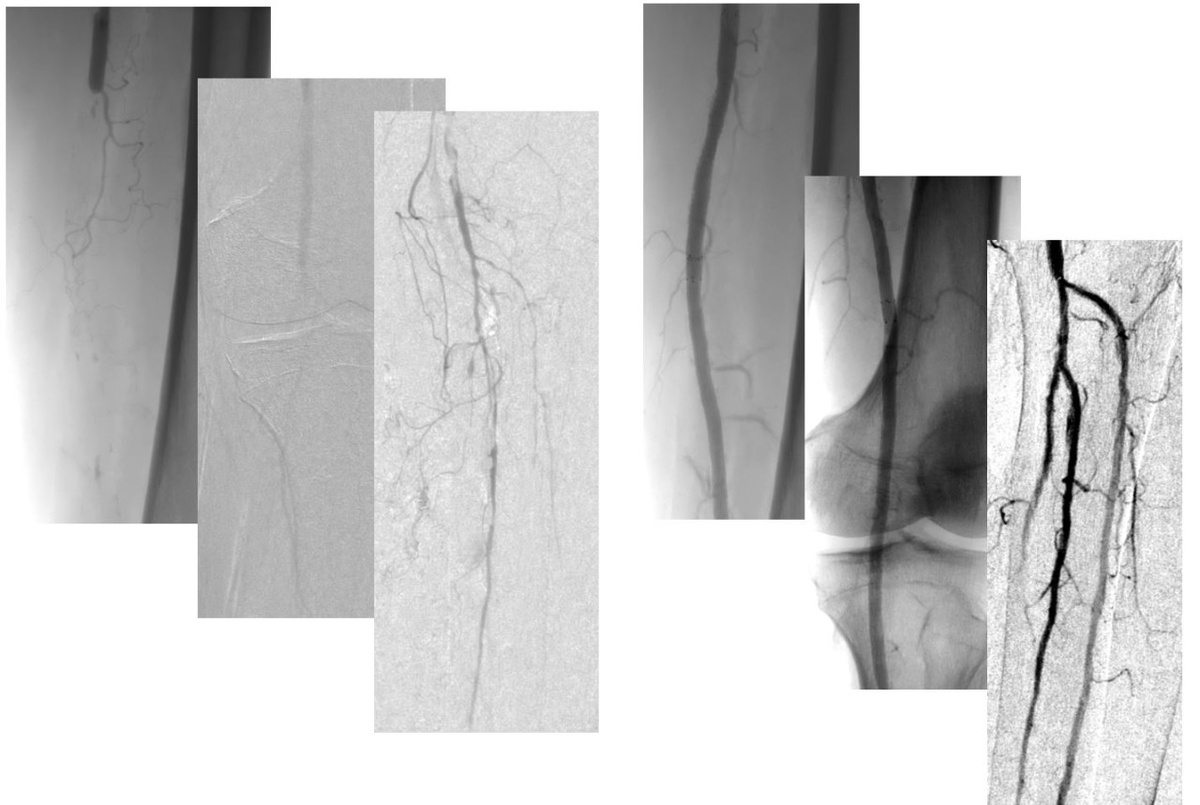

Эндоваскулярная реваскуляризация нижних конечностей

ПАЦИЕНТ 1, 83 ГОДА

В конце декабря 2021 г. обнаружен дефект кожи 1 пальца левой стопы, с умеренными болями покоя. Лечился дома, проводил перевязки с мазью Бетадин, проведен курс антибиотикотерапии.

Несмотря на лечение, язва не заживала, появились новые дефекты кожи на других пальцах левой стопы.

При обследовании в Ильинской больнице установлена ишемия, угрожающая левой нижней конечности на фоне сахарного диабета 2 типа и атеросклероза артерий нижних конечностей.

Чрезкожное напряжение кислорода:

Справа: тыл стопы - 53 mmHg

Слева: тыл стопы - 5 mmHg

Госпитализация на 1 (одни!) сутки, выполнено оперативное лечение в объеме эндоваскулярной реваскуляризации левой нижней конечности с прекрасным клиническим эффектом – боль полностью купирована.

ПАЦИЕНТ 2, 94 ГОДА

Сахарный диабет 2 типа много лет. Боль покоя в правой стопе более 1 года. Проходил лечение у неврологов по поводу диабетической нейропатии. После самостоятельно выполненного педикюра отметил появление ран на пальцах, которые не заживали.

При обследовании в Ильинской больнице установлена ишемия, угрожающая правой нижней конечности на фоне сахарного диабета 2 типа и атеросклероза артерий нижних конечностей.

Справа: тыл стопы - 43 mmHg

Слева: тыл стопы - 7 mmHg

Госпитализация на 3 суток, выполнено оперативное лечение в объеме эндоваскулярной реваскуляризации правой нижней конечности с прекрасным клиническим эффектом – боль полностью купирована.